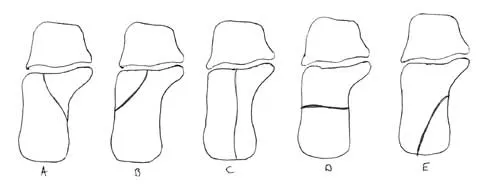

Question 59

In Figure 14, the primary fracture line in a calcaneal fracture is best depicted by which of the following schematics?

Explanation